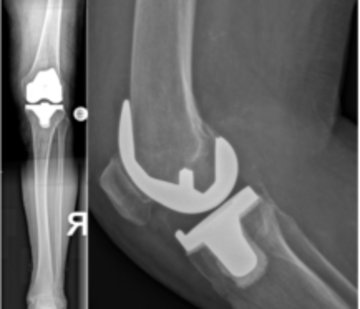

Teilgekoppelte und gekoppelte Knieprothesen

In bestimmten Situationen ist die natürliche Bandführung und Stabilität des Gelenkes nicht mehr vorhanden. In diesem Fall besteht die Möglichkeit, eine teilgekoppelte (semiconstrained) oder gekoppelte (achsgeführt, constrained, rotating hinge) Prothese zu implantieren.